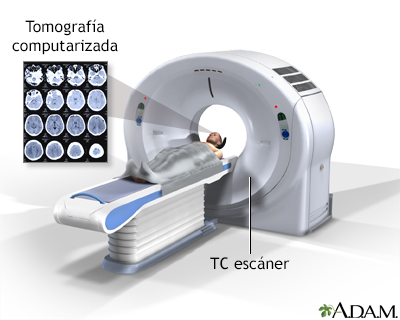

SALA DE TOMOGRAFÍA

CAMILLA

CABEZA MOVIL

GANTRY

DETECTORES

TUBO DE RX

DAS ( Data acquisition system)